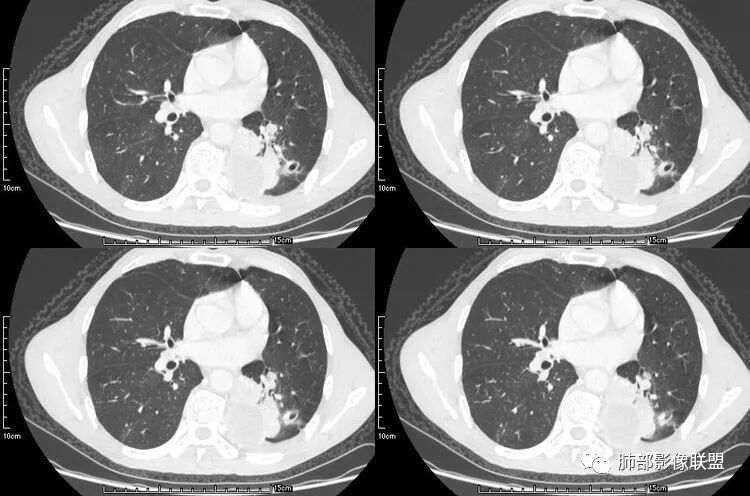

病例三

病史为结肠腺癌;双肺多发薄壁囊腔转移瘤

来源于杨凌婧.囊性空洞型肺转移瘤1例报告[J].实用医院临床杂志,2016,13(01):157-158.

本病例左肺下叶肿块,有深分叶、毛刺、胸膜牵拉凹陷、支气管截断及纵隔内淋巴结肿大等征象,都均支持病灶为恶性,如腺癌,而且叶间裂的多发结节也提示是腺癌来源可能大;双肺多发结节、肿块,大部分病灶有分叶、毛刺及胸膜凹陷的恶性征象,与原发肿瘤本身的性质有关,所以应该与左肺下叶肿块同源,而且双肺多发病灶内空洞也具有多样性;

此病例中空洞形态多样,内壁不光整,有分隔影,周围未见明显卫星灶及钙化灶,结核不太符合;患者病史慢性病史,无明显发热,缺乏中毒临床表现,急性感染基本排除;各种中性粒细胞胞浆抗体阴性,没有鼻窦炎,肾脏等病史,基本排除血管炎;霉菌性空洞常见于免疫机能低下者, 常为空洞、肺炎、伴“ 晕圈”征的结节及支气管扩张合并存在。